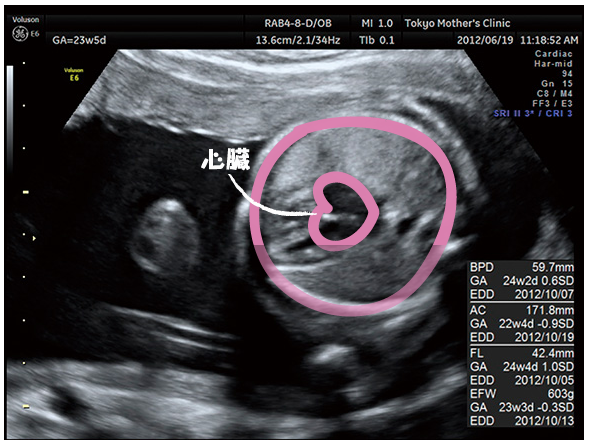

妊娠6ヶ月(20週・21週・22週・23週)の経過とエコー写真 20週3日(20w3d) 待ちに待った6ヶ月健診です。 20w3dの6ヶ月健診で性別が判明しました!!!!!!! ただ、この日は実はいつものエコーではなくて、4Dエコーを撮りました。. 性別が男の子から女の子に変わった先輩妊婦の体験談 体験談1 妊娠8ヶ月ごろに産婦人科の先生から「男の子で間違いないですよ」言われました。 私も確かにエコーで男の子の象徴をちゃんと見ました。. 今日で妊娠15週6日目、明日からは安定期と呼ばれる妊娠5ヶ月目に突入です。 もうね、最近本当にぐーたらした生活を送っておりまして(´ω`。)グスン ブログの更新どころか、仕事すら手についてないっていう。。。 つわりも落ち着いてきたのに、完全に堕落した生活を送っております。.

妊娠23週3日 23w3d の超音波 エコー 写真

妊娠22週 エコー写真で見る胎児の大きさ 胎動 22週の壁とは 妊娠中期 All About

妊娠21週目エコー写真 胎動の様子 胎児の大きさや体重 性別 妊娠中期 All About

妊娠23週目 23w0d 6d のエコー写真とエピソード 妊娠6ヶ月 Cozre コズレ 子育てマガジン